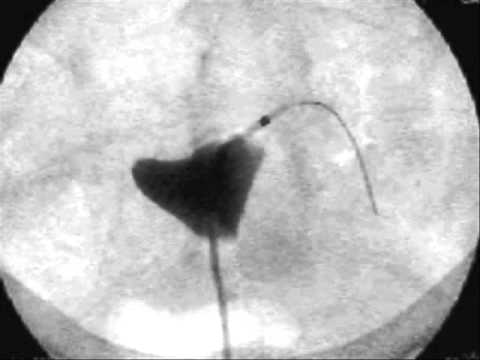

Opening a fallopian tube

Fallopian Tube Blockage course, in this course we'll delve into the causes, diagnosis, and treatment options for fallopian tube blockage. Participants will learn about the various factors contributing to blockages, including infections, endometriosis, and pelvic inflammatory disease. Understanding these aspects is crucial for individuals seeking to address infertility or reproductive health issues related to fallopian tube obstruction.